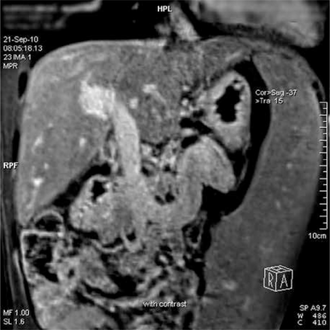

In addition, a widened (dilated) portal vein as seen on a CT scan or MRI may raise the suspicion about portal hypertension. A cutoff value of 13 mm is widely used in this regard, but the diameter is often larger than this is in normal individuals as well.[7]

A dilated portal vein (diameter of greater than 13 or 15 mm) is a sign of portal hypertension, with a sensitivity estimated at 12.5% or 40%.[13] On Doppler ultrasonography, a slow velocity of <16 cm/s in addition to dilatation in the main portal vein are diagnostic of portal hypertension.[14] Other signs of portal hypertension on ultrasound include a portal flow mean velocity of less than 12 cm/s, porto–systemic collateral veins (patent paraumbilical vein, spleno–renal collaterals and dilated left and short gastric veins), splenomegaly and signs of cirrhosis (including nodularity of the liver surface).[12]